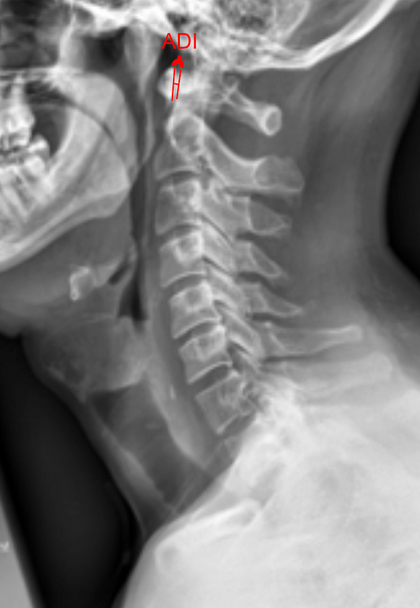

The Atlantodental Interval (ADI)—also known as the atlantoaxial interval (AAI)—is the distance between the posterior surface of the anterior arch of the atlas (C1) and the anterior surface of the odontoid process (dens) of the axis (C2).

This measurement assesses the integrity and stability of the transverse atlantal ligament (TAL), which stabilizes the atlantoaxial joint. An increased ADI suggests instability at the atlantoaxial junction, potentially due to trauma, rheumatoid arthritis, congenital anomalies, or ligamentous laxity.

• Obtain a neutral lateral cervical spine X-ray (as shown in the provided image).

• Identify the anterior arch of C1 (atlas) and the odontoid process (dens) of C2.

• Draw a line along the posterior border of the anterior arch of C1.

• Draw a line along the anterior border of the odontoid process.

• Measure the shortest distance between these two lines—this is the ADI.

• Normal ADI (adults): ≤ 3 mm

• Pathologic/Unstable ADI (adults): > 3 mm (suggests transverse ligament instability)

• Normal ADI (children): ≤ 5 mm

• Pathologic/Unstable ADI (children): > 5 mm (physiologic laxity greater than adults)